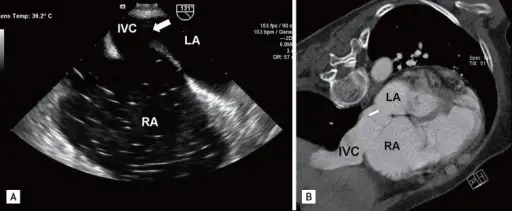

Atrial Septal Defect (ASD)

An atrial septal defect (ASD) is a hole in the wall that separates the right and left atria.

Paradoxical emboli are potential complications of atrial septal defects (ASD).